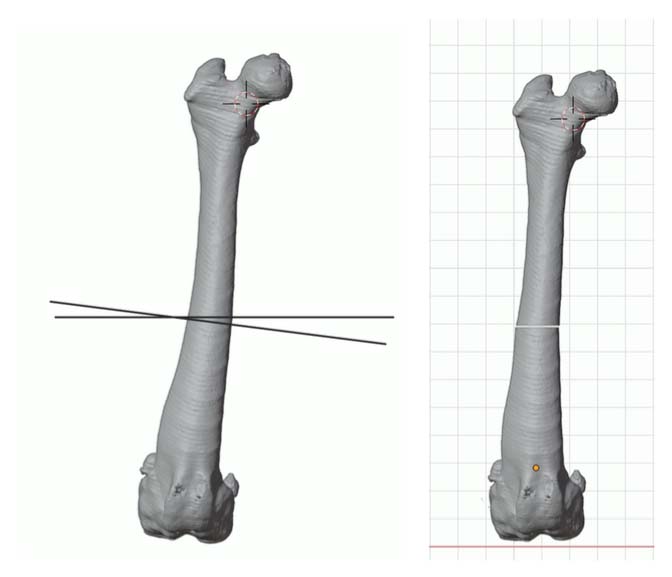

A method of planning and correction, commonly used in human surgery, has been adapted for the small-animal patient. This method is called the center of rotation of angulation (CORA). With this method, bone axes and joint orientation angles were made to provide guidance for accurate correction of angular limb deformities based on one standard set of geometric principles as they apply to osteotomies, regardless of the bone in question or the type of fixation device.

CT CAD-based approach to deformity planning documented two right femoral deformities:

Excessive anatomical lateral distal femoral angle (aLDFA) = 88.8 degrees

Femoral version 20 degrees

Correct the right femur angular limb deformities with a mid-diaphyseal oblique closing-wedge ostectomy centered at the CORA of the femoral deformity, which is located within the mid-diaphyseal (do not recommend a traditional distal femoral ostectomy (DFO) as this would result in a significant lateral femoral translation in this specific case). The trochlea is arthritic and hypoplastic, but not overtly deformed. In this case, a traditional block or wedge trochleoplasty is recommended rather than a patellar groove replacement (PGR). In addition, a corrective de-torsional tibial osteotomy has been recommended, as a tibial tuberosity transposition (TTT) is unlikely able to compensate for a torsion of this magnitude.

CT CAD-based surgical plan.